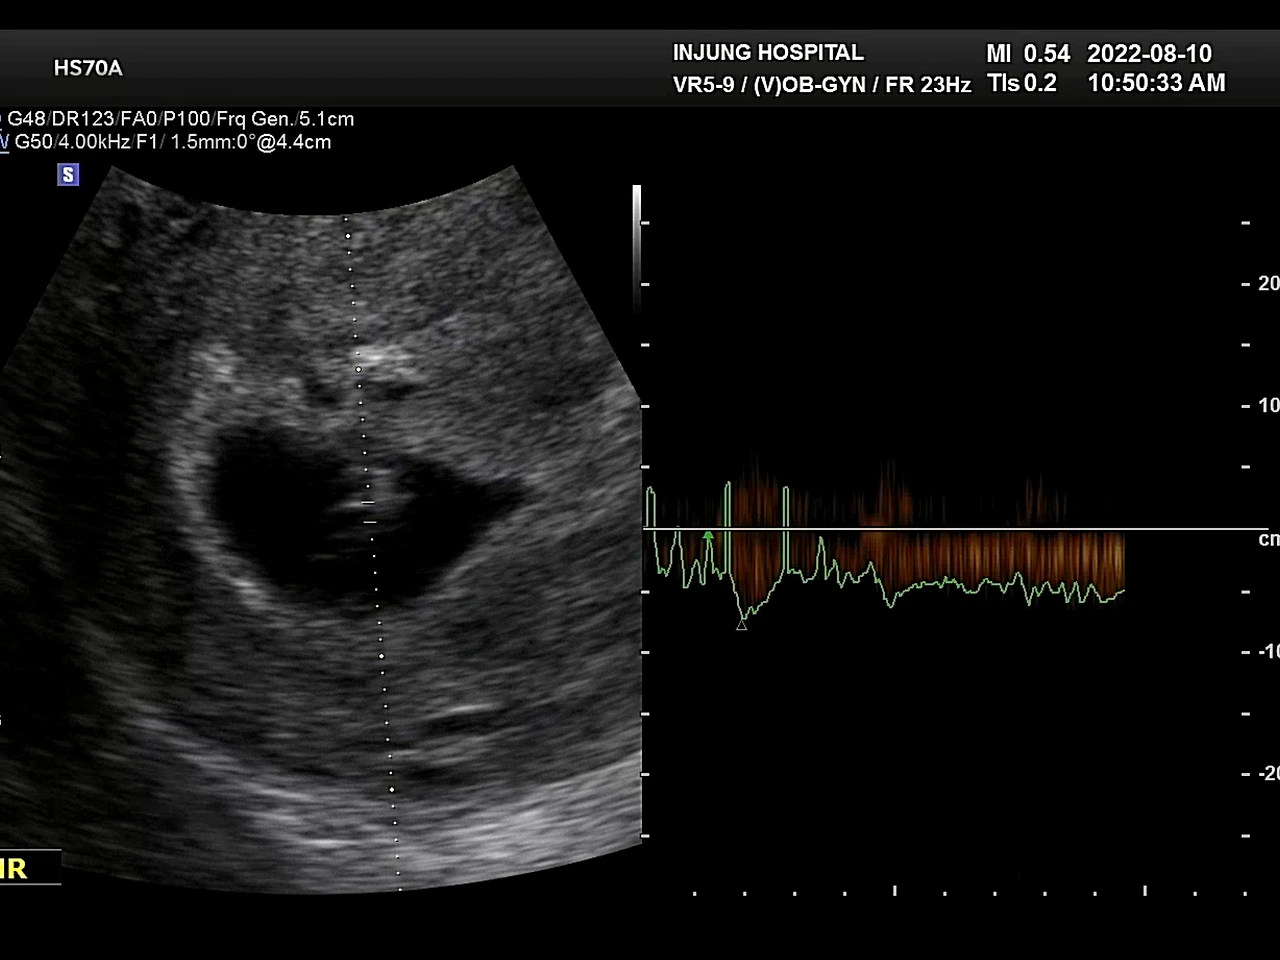

테스트기를 하고 1주일 뒤 병원을 찾았다. 아기집을 보고 젤리곰같은 태아도 봤다. 심장도 잘 뛰고 있었다. 벌써 6주 6일. 혹시나 임신이 아니면 어쩌지, 다른 문제가 생긴거면 어떡하지라는 걱정들이 무색했다.